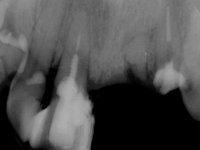

Paciente do sexo masculino, com 64 anos de idade, não fumador, recorreu á minha consulta após traumatismo do sector anterior. Os dentes 2.1 e 2.2 apresentavam extensas fraturas infra ósseas. Os dentes 1.2 e 1.1 apresentavam-se ferulizados com uma resina composta na zona inter-proximal. O dente 1.1 apresentava um tratamento endodôntico sofrível e um poste intra-radicular. O dente 1.2 estava vital e tinha uma extensa restauração da resina composta. Estando ferulizados, não foi possível avaliar o grau de mobilidade dentária de cada um dos dentes, mas o conjunto não tinha mobilidade. Após exame clínico e Imagiológico conclui-se que as raízes dos dentes 2.1 e 2.2 tinham extração indicada. O paciente estava reabilitado provisoriamente com uma prótese removível esquelética com 3 dentes. Apresentava algum comprometimento periodontal e os dentes mostravam as superfícies oclusais e incisais desgastadas. Higiene oral razoável.

Foi proposta a extração das raízes dos dentes 2.1 e 2.2. e colocação de 1 implante no local do dente 2.1 que suportaria uma ponte aparafusada com 2 elementos. O dente 2.1 sobre o implante e o 2.2 em extensão. Se em termos periodontais a zona do 1.2 e 1.1 continua-se a maturar sem problemas e se garantir-se um bom suporte sem mobilidade, seria proposto refazer o tratamento endodôntico do 1.1 e fazer o tratamento endodôntico no 1.2. Posteriormente e após colocação de postes intra-radiculares os dentes seriam reabilitados com uma ponte com 2 elementos. Após a colocação da ponte de2 elementos sobre o implante colocado no local do 2.1, o paciente sofre um novo traumatismo que compromete a viabilidade dos dentes 1.2 e 1.1. Nessa altura é proposta a colocação de um novo implante no local do dente 1.1 e confeção de uma ponte de 4 elementos com os dentes 1.1 e 2.1 sobre os implantes e os dentes 1.2 e 2.2 como pônticos em extensão.

Primeira Fase

Foram feitas as extrações das raízes dos dentes 2.1 e 2.2 porque estavam a incomodar. Após 3 meses de cicatrização fez-se o exame imagiológico e estudo implantar para colocação do implante no local do 2.1.Foi colocado um implante de 4.1mm de diâmetro por 10mm de altura, colocado ao nível ósseo. Passados 2 meses após a cirurgia implantar, foi feita a segunda cirurgia para colocação de um parafuso de cicatrização. Foi feita a impressão ao implante com técnica de moldeira aberta com silicone de dupla viscosidade um mês após. No laboratório foi confecionada uma infraestrutura metálica para uma ponte de 2 elementos aparafusada ao implante. Esta infraestrutura apresentava 2 apoios palatinos para ajudar a estabilizar os dentes 1.1 e 2.3 a recuperar do traumatismo. Recuperados os dentes, os apoios poderiam ser retirados. Esta peça apresentava uma conexão interna ao implante com sistema anti-rotacional. A prova da infraestrutura foi feita em boca sendo o seu correto ajuste verificado com controle imagiológico. No revestimento da infraestrutura foi utilizada cerâmica de tonalidade coronária e gengival. Depois de verificada em boca e aprovada pelo paciente a ponte foi apertada definitivamente e o orifício de acesso obturado.